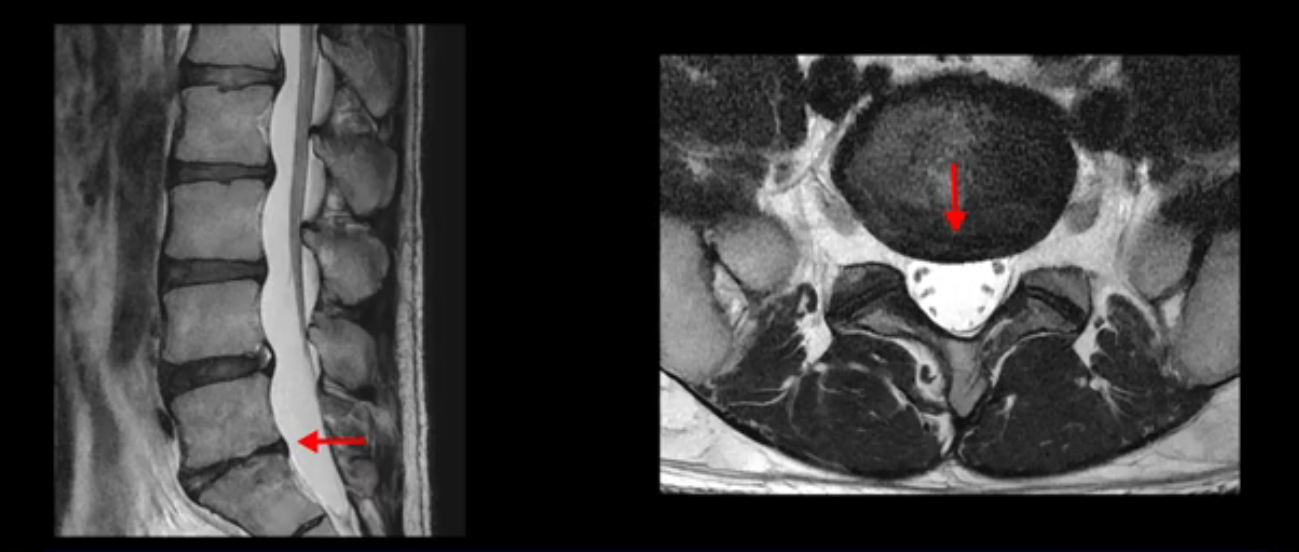

5번 1번 역시 가운데로 디스크 조금 밀려 나와있지만 신경 공간 넓이는 아주 넓어서 신경 눌림 있을 거라고 예상이 안됩니다.

추간공도 보시다시피 왼쪽, 오른쪽 전부 다 매우 넓어서 신경이 눌릴만한 부분이 전혀 보이지 않습니다.

앞서 1번 2번, 4번 5번, 5번 1번의 디스크가 찢어지고 조금 밀려 나온 게 최근에 찢어진 게 아니고 오래된 걸로 보인다고 말씀 드렸죠. 왜 그럴까요? 만약 급성으로 찢어진 것이라면 아주 심한 디스크성 통증이 있겠죠. 기침이나 재채기를 하면 심하게 아프고 허리를 조금만 구부리거나 비틀면 아주 날카로운 통증들이 생길 겁니다. 그런데 이분은 이런 증상이 전혀 아닙니다. 또 디스크의 밀려나온 정도도 전혀 심하지 않기 때문에 이분이 가지고 계신 양쪽 다리 저림, 특히 이분은 누워있을 때도 양쪽 발이 발가락까지 쑤신다고 하는데 이정도 디스크 때문에 그런 증상은 생길 수가 없는 겁니다. 이처럼 이분의 가벼운 디스크 탈출은 이미 오래 전에 진행되었고 섬유륜 자체는 이미 아문 상태인데도 디스크내장증을 진단받은 환자들 중에는 본인이 섬유륜 파열 환자라고 끝까지 믿는 분들이 많습니다. 다시 말하지만 디스크내장증이라는 진단을 받은 환자들을 보면 거의 전부 다 섬유륜 파열 증상이 아닙니다. 증상이 완전히 다릅니다. 진단이 애초에 잘못되면 어떤 치료를 받아도 좋아질 수 없습니다.

이 HIZ는 섬유륜이 찢어졌다가 이미 아문 뒤에도 얼마든지 보일 수 있는 흔적일 가능성이 있어서 재채기를 하면 아픈지, 허리를 구부릴 때 날카로운 통증이 생기는가 등의 증상으로 구별해야 하는데 MRI만 보고 HIZ가 보이면 그게 마치 통증의 원인인 것처럼 얘기하는 의사들이 있습니다. 이분 MRI를 자세히 보고 증상을 정말 자세히 들어본 의사가 있었더라면 다른 환자분들처럼 증상과 MRI가 일치하지 않는다는 얘기를 들을 수 있었을 텐데 이분은 그런 얘기는 듣지 못했습니다.